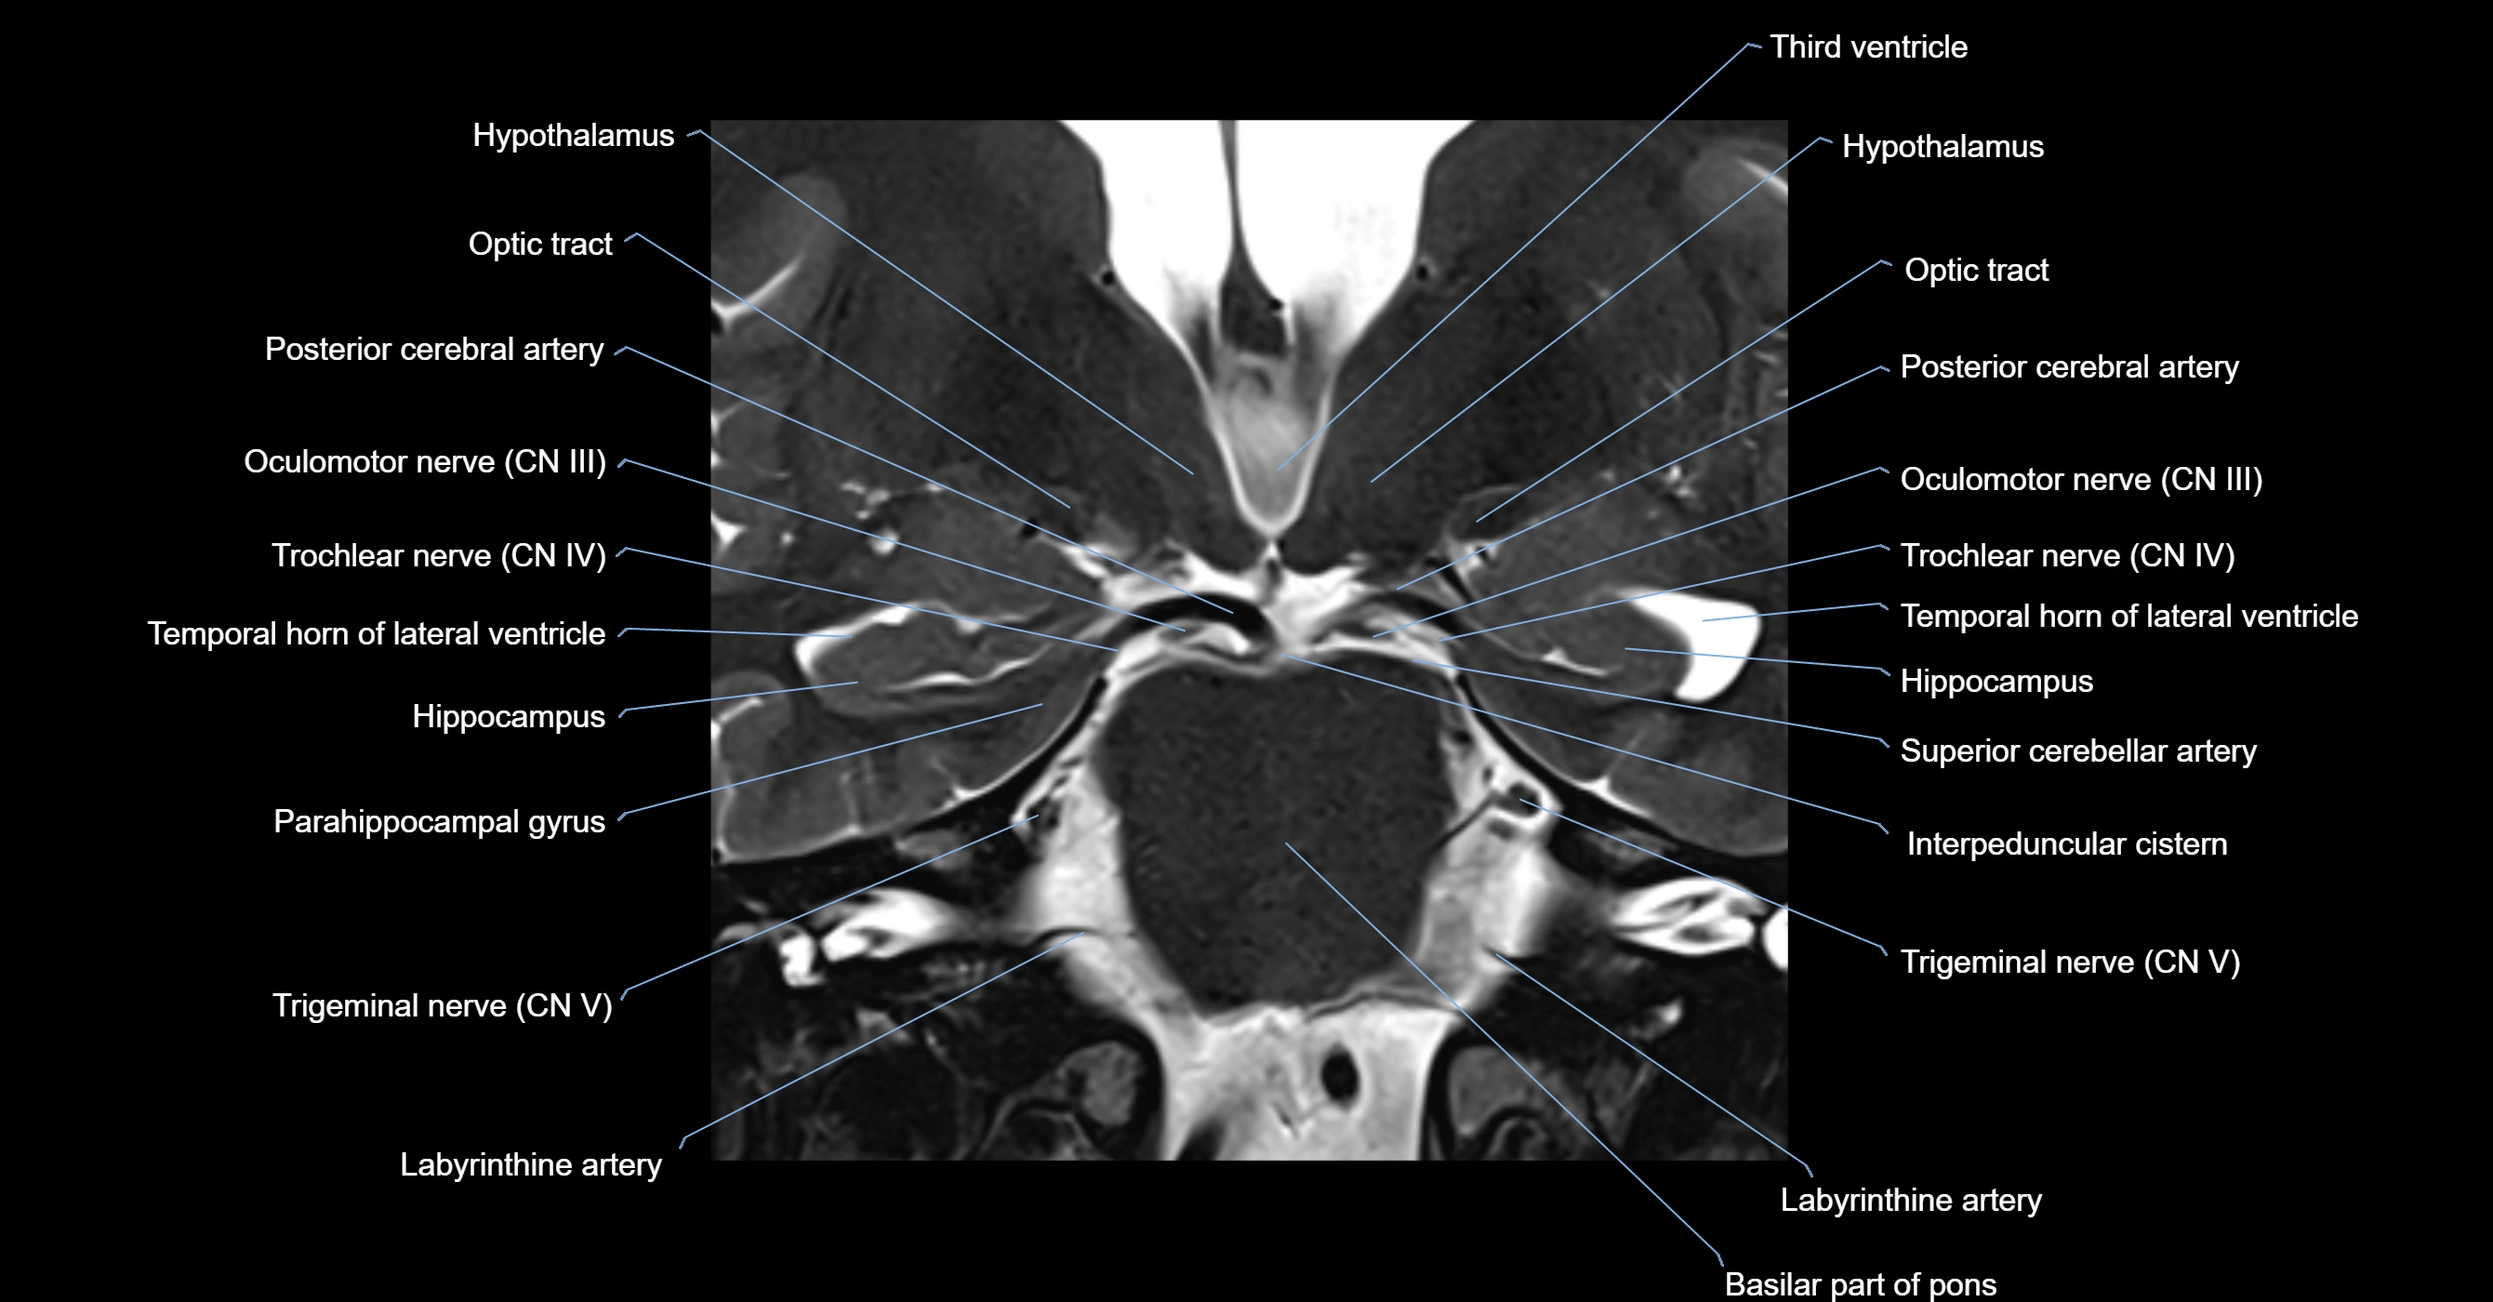

MRI Appearance

The abducens nerve is a small, thin, linear structure

Best visualized on high-resolution T2-weighted 3D MRI sequences (e.g., FIESTA or CISS)

Seen as a hypointense (dark) line running from the brainstem at the pontomedullary junction, traversing the prepontine cistern, and entering Dorello’s canal under the petrosphenoidal ligament, then into the cavernous sinus, and finally the orbit

May be challenging to visualize in standard MRI due to its small size

Pathology may be inferred by absence, displacement, or enhancement of the nerve

MRI images